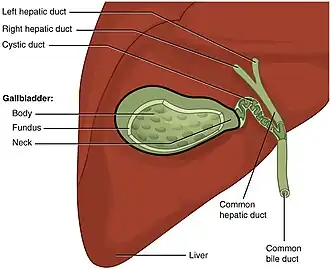

Gallbladder

The gallbladder is a hollow pear-shaped organ located posterior to the inferior middle part of the right lobe of the liver. It is variable in shape and size. It stores bile before it is released into the small intestine via the common bile duct to help with digestion of fats. It receives bile from the liver via the cystic duct, which connects to the common hepatic duct to form the common bile duct.[21]

The gallbladder gets its blood supply from the cystic artery, which in most people, emerges from the right hepatic artery.[21]

Gallstones is a common disease in which one or more stones form in the gallbladder or biliary tract. Most people are asymptomatic but if a stone blocks the biliary tract, it causes a gallbladder attack, symptoms may include sudden pain in the upper right abdomen or center of the abdomen. Nausea and vomiting may also occur. Typical treatment is removal of the gallbladder through a procedure called a cholecystectomy.[22][23] Having gallstones is a risk factor for gallbladder cancer, which although quite uncommon, is rapidly fatal if not diagnosed early.[24]